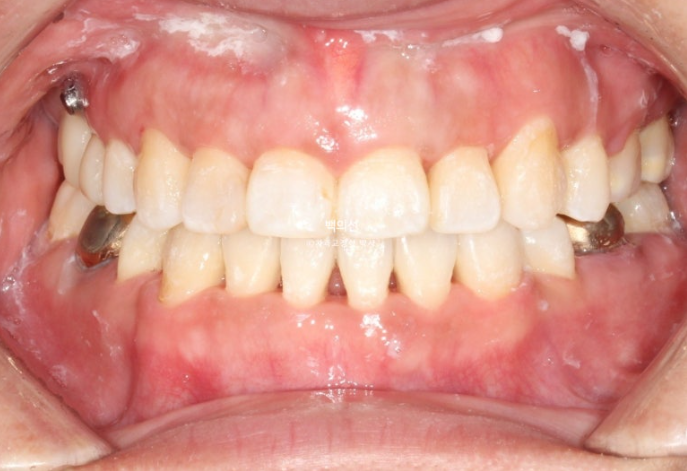

이후 발치공간 폐쇄 및 교정용 나사인 미니스크류를 이용한 거미스마일 개선 치료를 더 진행 후 25년 6월, 치료를 마무리 했습니다. 총 치료기간은 2년 6개월입니다.

25.06

교정과 크라운치료를 모두 마친 후 클리피씨 브라켓을 제거한 모습입니다.